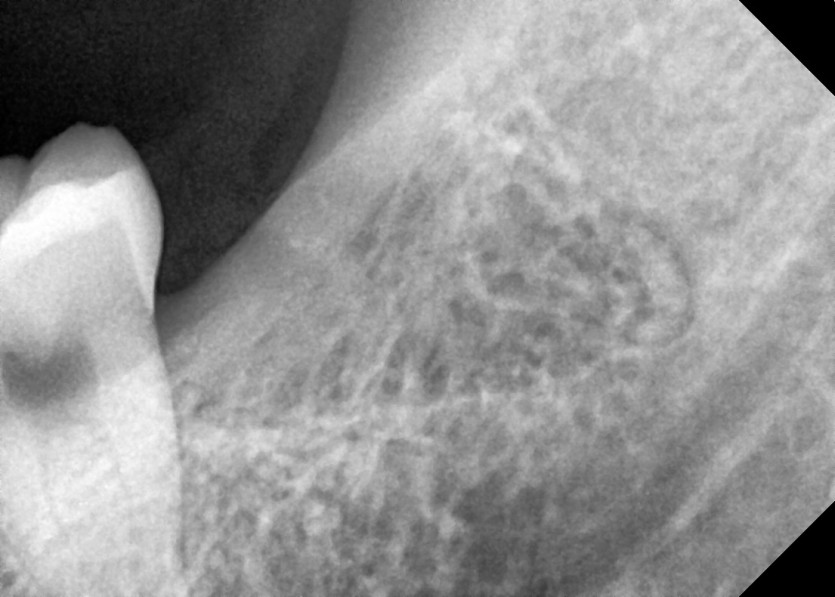

#18,28,38,48 사랑니 발치

구강 외과 전문의가 당일 발치했습니다.